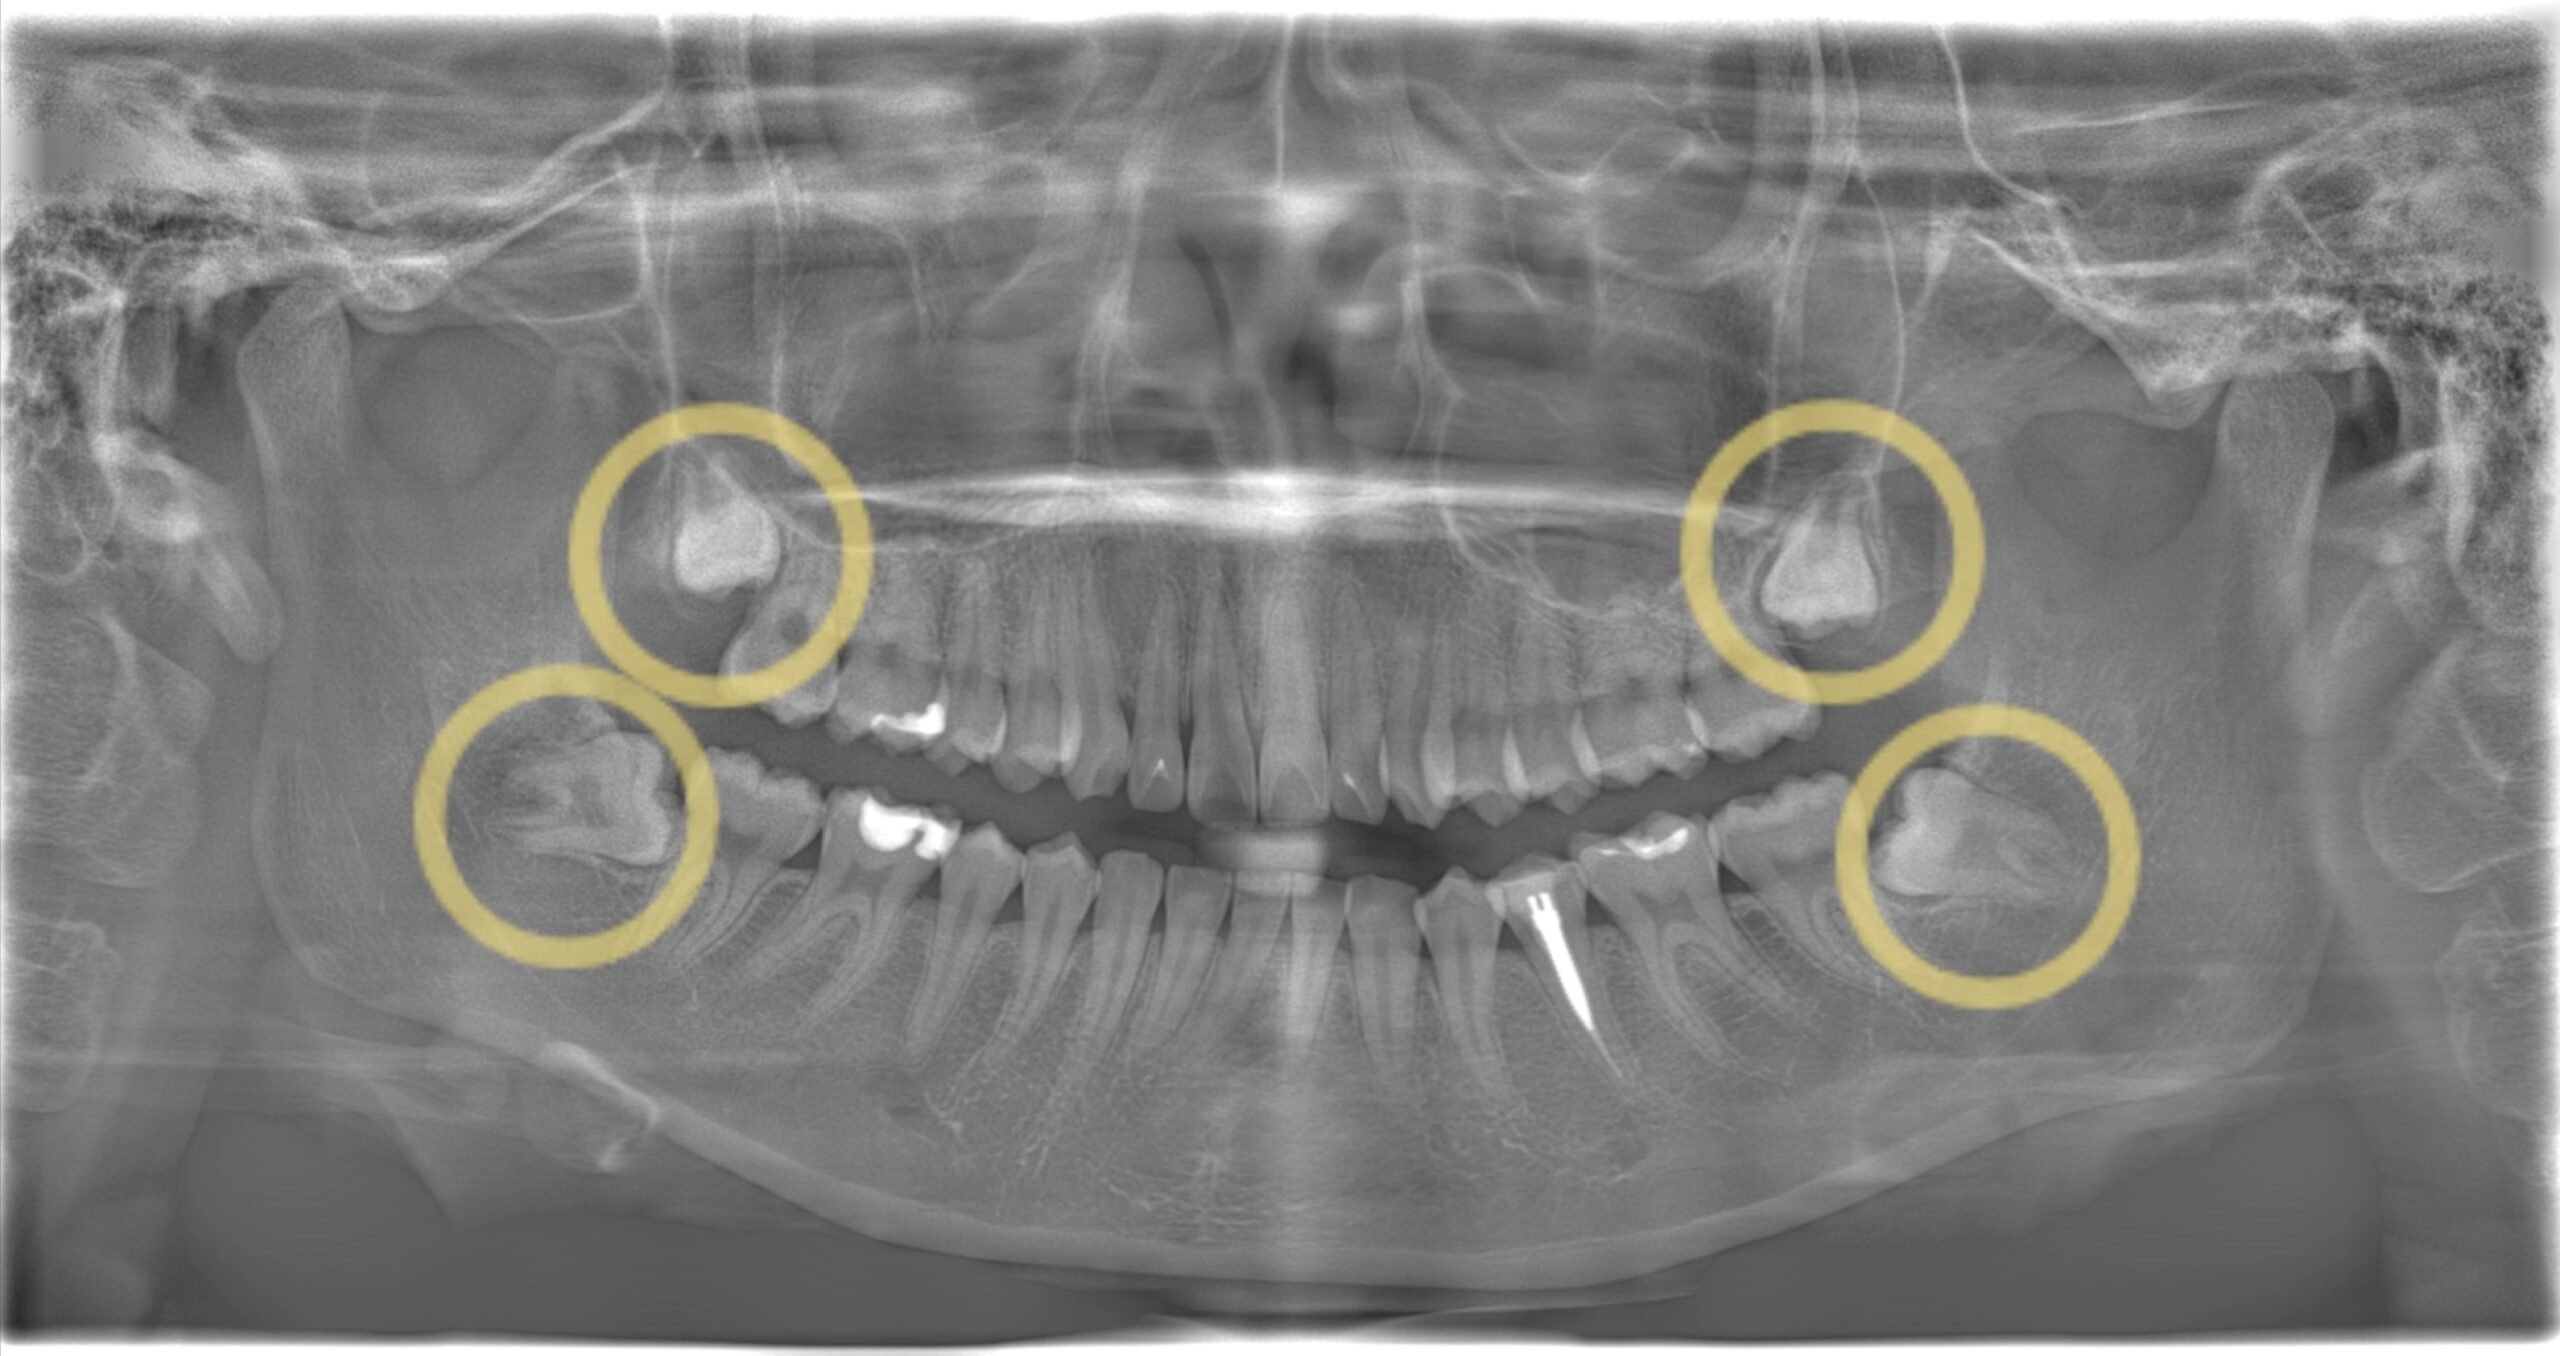

こちらのレントゲンをご覧下さい。

黄色の丸で囲っている所が親知らずです。

基本的に前から数えて8番目の歯になります。

上は真っ直ぐ生えていますが、下は横向きに生えているのが分かりますね。